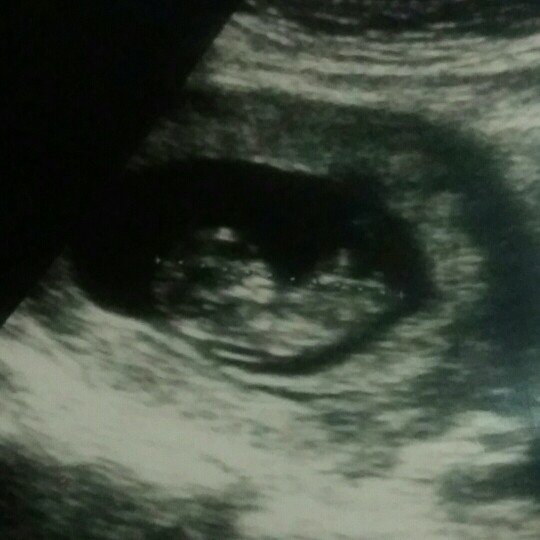

11 week